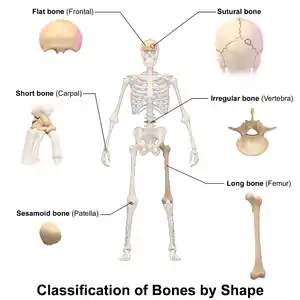

Flat bones in human skull. (shown in red) Classification of bones by shape.

Classification of bones by shape.